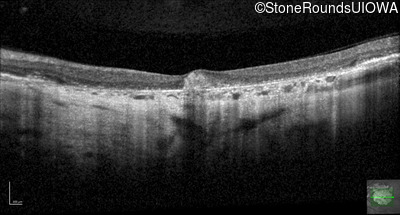

Optical Coherence Tomography - Right - 10/300

Exemplar / OCT Stack